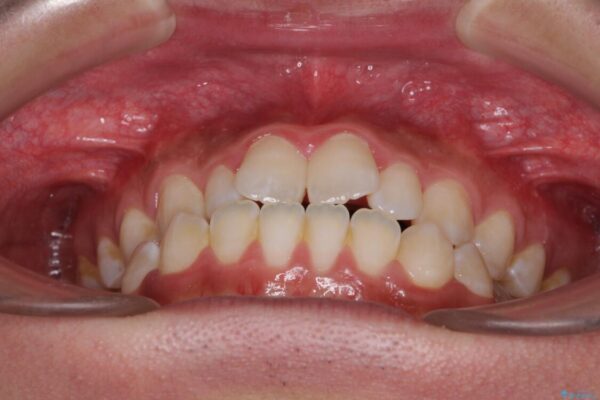

治療前

• 口元の突出感を改善 受け口傾向の咬み合わせの抜歯矯正 治療前画像